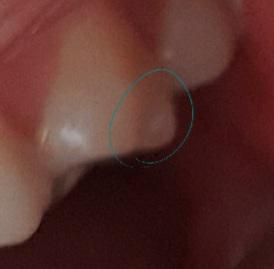

이빨 겉부분이 살짝 깨졌는데 괜찮을까요?

사진처럼 이빨 겉부분이 살짝 깨졌는데 괜찮을까요? 물마셨을때 시리거나 아프지 않으니 신경에는 닿지 않는것 같습니다. 둥글게 다듬어 질때까지 자제해야 할 음식이라도 있을까요?

• 1번 째 사진